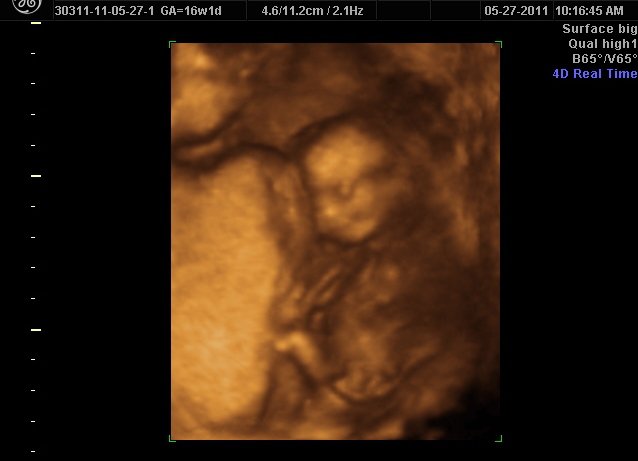

I went in for my 18 week ultrasound and unfortunately they weren't able to tell for sure what the gender was. The tech said 75% girl but I think because they hasn't seen a male part. Has anyone had a similar experience.

I'm super anxious to find out the gender for planning purposes. I can't go in again until 28 weeks and I just can't wait that long. Has anyone gotten a 3d ultrasound to reveal the gender?